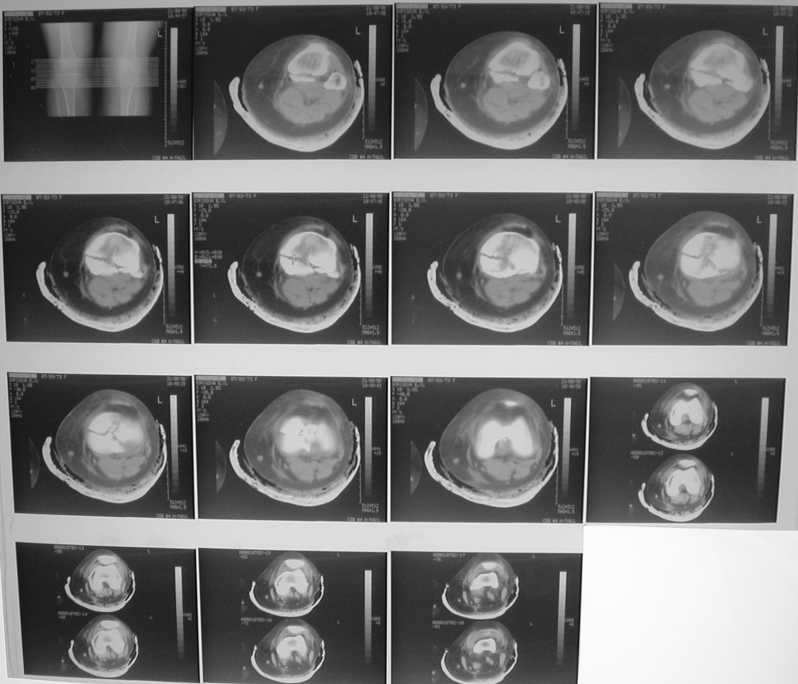

Проблема тут, видимо, не в выборе имплантата, а в том, что надо делать остеосинтез задним доступом. А пластинка подойдет практически любая - небольшая T-образная, хоть две 1/3 трубчатых. Угловая стабильность необязательна. Лишь бы трансплантат не вываливался. На КТ хорошо бы увидеть еще и срезы в сагиттальной и фронтальной плоскостях.